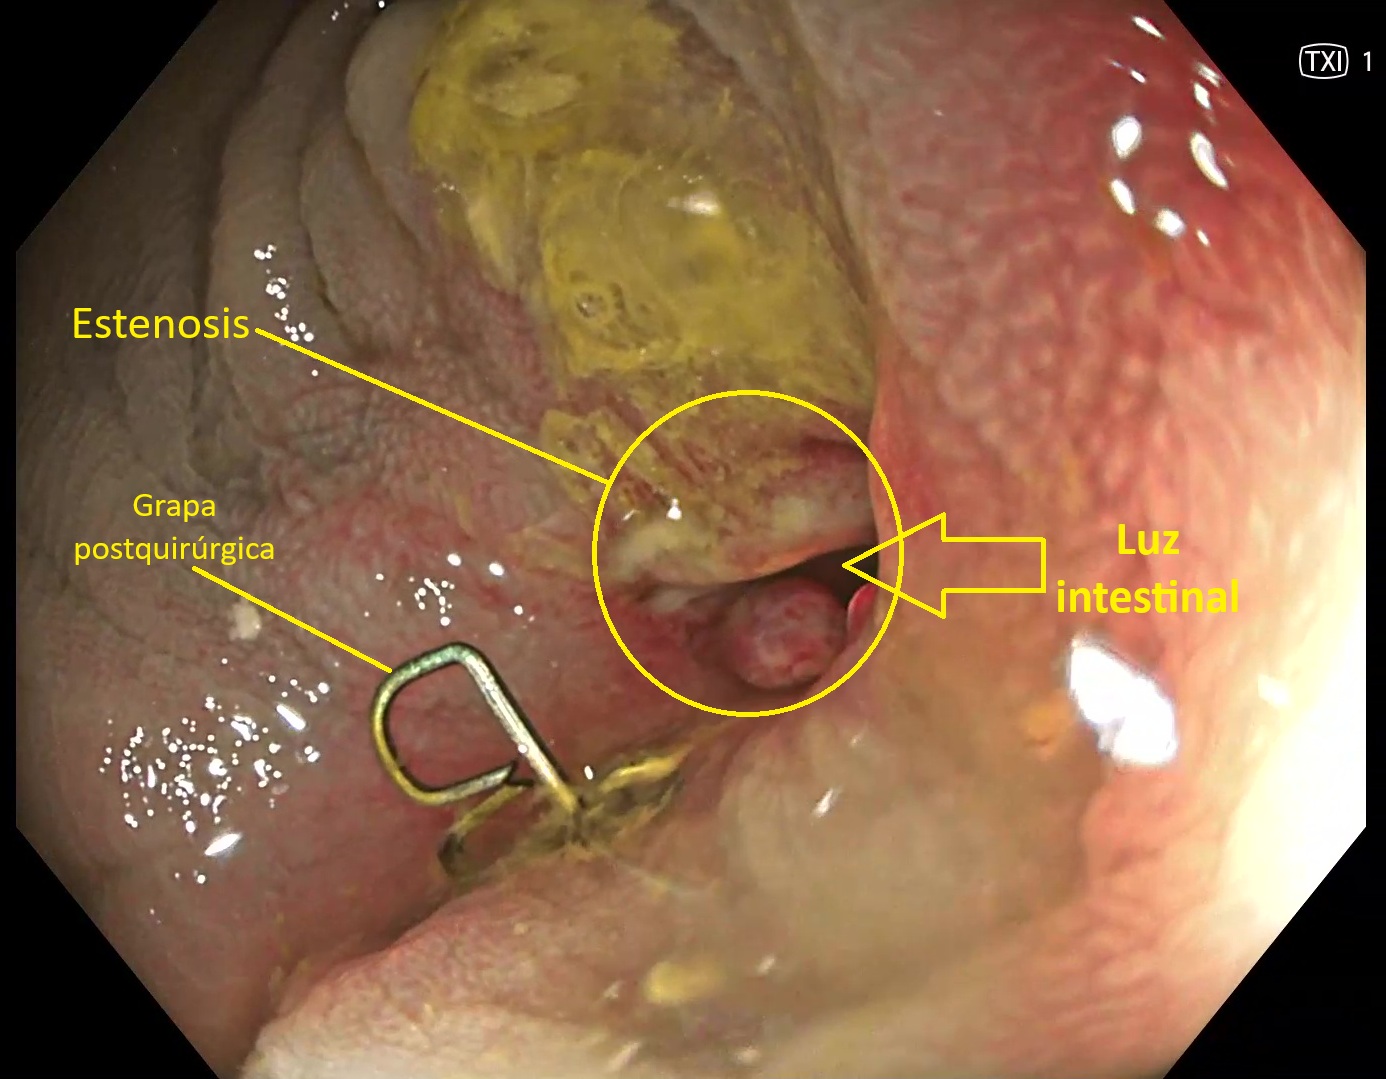

Las estenosis colónicas son estrechamientos de la luz del colon que pueden ser consecuencia de inflamación crónica o por cirugía previa. Esta última, habitualmente asociada a extirpaciones previas de segmentos del colon por cáncer.

En la colonoscopia, la estenosis aparece como un área de luz reducida. Puede tener asociados cambios inflamatorios en su superficie, tanto si están asociadas a enfermedad inflamatoria intestinal como si son debidas a cirugías previas.

En este último caso se suelen ver puntos de sutura de la cirugía o grapas. La mayoría de las veces responden adecuadamente a las dilataciones endoscópicas con balón,